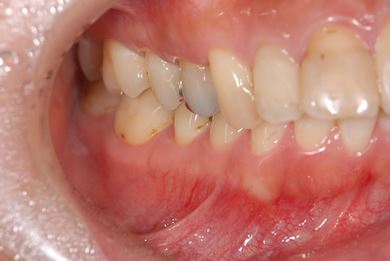

性別/年齢 女性 / 27歳

主訴 他の歯科医院に4ヶ月通院していたが、違和感が治らない。

治療内容 オールセラミック4本(セラミック用の土台4本)

2 1 1 2

総治療費 573,300円

治療期間 9ヶ月

治療後